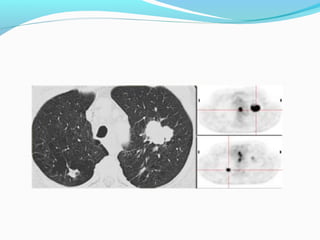

FDG UPTAKE

STAGE ??